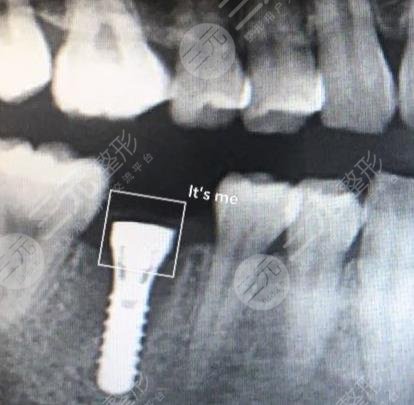

二、杭州美奥口腔医院种植牙案例分享

我的牙齿是因为一次过年吃甘蔗的时候不小心给搞掉了的,后来一直也没有补它,但是近来因为没有管它,导致有食物残留进入了牙缝使得牙齿发炎的了,到了医院进行检查后,医生告诉建议我做种植牙,把这颗牙补上,如果不补的话,对于牙齿是很不好的,所以我就决定了做种植牙手术。

整个手术的过程是比较久的,因为中间有一个恢复的过程,比较麻烦的就是种植体的安装,这个过了后面就好了很多,现在我的牙齿已经种好了,这颗牙和之前的牙差别也不是很大,并且用起来也是非常舒服的,没有什么不适的感觉,整体是很棒的。